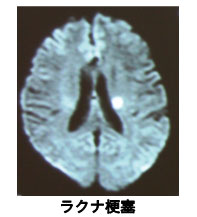

• 脳梗塞には幾つかのタイプがあり、細い血管が狭くなって詰まる「ラクナ梗塞」、太い血管が動脈硬化で狭くなったことで生じる「アテローム血栓性脳梗塞」、心臓内で生じた血のかたまりが血流に乗って脳まで運ばれる「心原性脳塞栓症」が代表的です。脳梗塞のタイプを様々な検査で診断し、治療法・予防法を選択します。